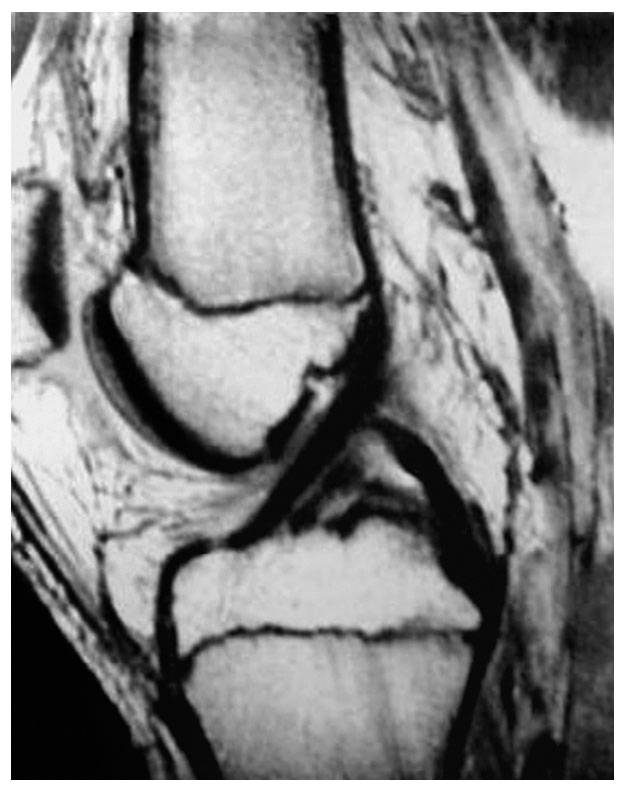

磁共振成像正常前交叉韧带影像

磁共振成像以其优质的图像、对人体的无创性而受到越来越多的重视。磁共振成像应在冠状面和矢状面两个平面上扫描影像,扫描厚度每层3~5mm以获得交叉韧带的低密度影像。如果影像连续性中断,则可以判断韧带损伤。磁共振成像对于前交叉韧带损伤有很高的诊断价值,它的敏感性92%~100%,特异性89%~97%。